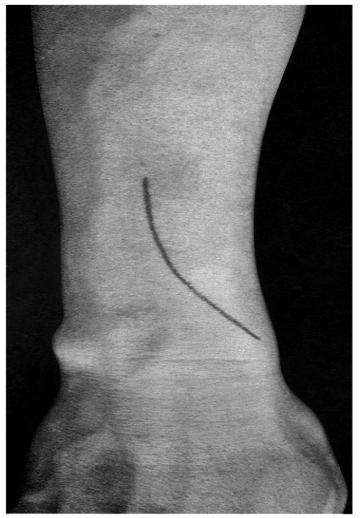

术前拍腕关节正、侧位X线片,腕关节冠状位、矢状位和水平位CT(图2-2)。此患者骨缺损和无法闭合复位的骨片均在背侧,宜采用背侧入路,复位,植骨,固定。取患肢前臂远端桡背侧纵切口(图2-3),从伸拇长肌腱和桡侧伸腕长、短肌之间进入,注意保护血管神经和肌腱,显露清理折端骨缺损区域和背侧移位的骨片(图2-4),复位,植骨,外固定架超关节固定(图2-5、图2-6)。术中透视骨折复位固定满意(图2-7),术后拍X线片证实(图2-8)。此手术的优点在于避免了局部存在内固定物的刺激,避免二期切开取出固定物所致的再次损伤。

图2-3 切口起自桡骨茎突,向上沿桡骨后缘并略偏向尺侧